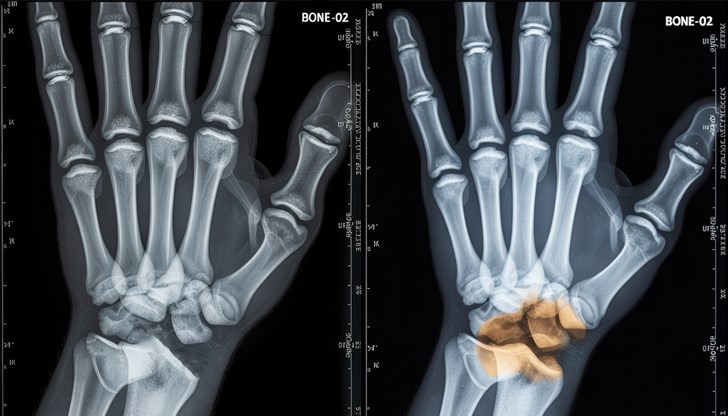

Китайски изследователи твърдят, че са създали революционно „костно лепило", способно да възстанови счупена кост само за минути. Според местни медии продуктът, наречен „Bone-02", вече е приложен успешно в клиничен случай, при който пациент с фрактура на китката е бил излекуван след еднократна инжекция.

По информация на китайските медии, пациент с фрактура на китката е получил 3-сантиметров разрез, в който е инжектирано лепилото. Костните фрагменти са били стабилизирани за минути, а след три месеца контролен преглед е показал пълно заздравяване без усложнения.